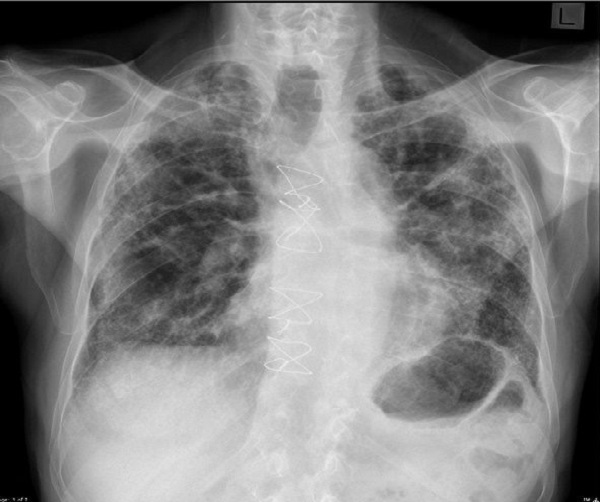

1. Biến chứng phổi: Ho khan, khó thở kéo dài dẫn tới việc phụ thuộc thở oxy. Tình trạng này do người bệnh bị xơ phổi không hồi phục (1 hoặc 2 bên phổi). Đặc biệt, tình trạng suy hô hấp sẽ càng trầm trọng trên nền người bệnh có sẵn bệnh lý hô hấp như bệnh phổi tắc nghẽn mãn tính, lao phổi, hen phế quản, viêm phế quản mãn tính…

Đặc biệt, đối với những người có sẵn bệnh nền như bệnh tim mạch, tiểu đường, đặc biệt là người mắc bệnh hô hấp đã kể trên, di chứng hậu COVID-19 có thể khiến tổn thương vốn có đó trở nên nặng hơn.

Bên cạnh đó, một số người khỏi bệnh sau khi mắc COVID-19 nghiêm trọng có thể xuất hiện những bất thường cận lâm sàng như tăng men tim kéo dài, rối loạn đường huyết, rối loạn nội tiết tố tuyến giáp, giảm độ lọc cầu thận; rối loạn chức năng hô hấp…